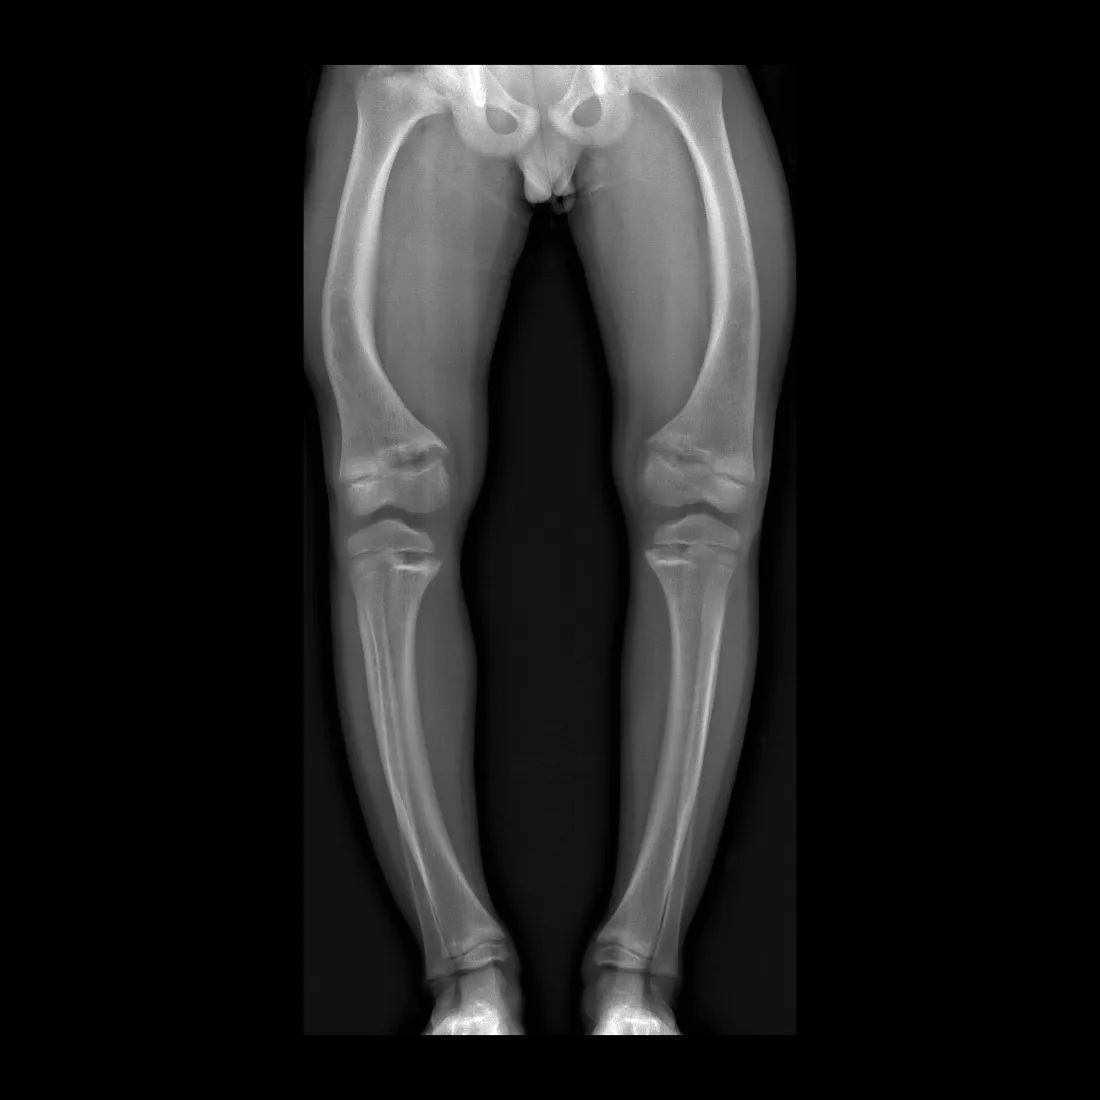

What is the best imaging modality to diagnose rickets?

Plain X-rays.

What is seen on X-rays of a rickets patient?

Bowed legs and widened wrists due to metaphyseal cupping.

What is the most common symptom of rickets?

Bowed legs.